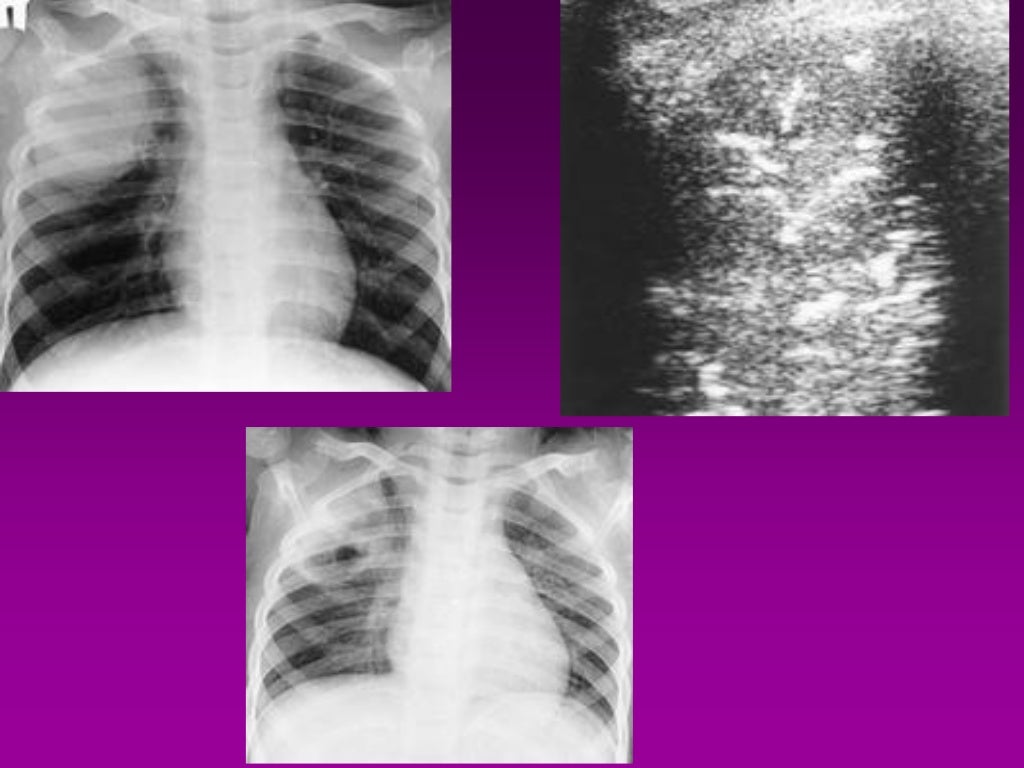

Basics of Chest Sonography and Anatomy of Chest Wall What The Meaning Of Chest Wall the chest wall is a complex system that provides rigid protection to the vital organs such as the heart, lungs, and liver; your thoracic cavity is a space in your chest that contains organs, blood vessels, nerves and other important body structures. the vertical bone of the chest, the sternum, defines the anterior chest wall. the. What The Meaning Of Chest Wall.

Basics of Chest Sonography and Anatomy of Chest Wall What The Meaning Of Chest Wall The three separate bone segments of different sizes and shape. your thoracic cavity is a space in your chest that contains organs, blood vessels, nerves and other important body structures. the chest, properly called the thorax, is the superior part of the trunk located between the neck and abdomen. the chest wall is a complex system that. What The Meaning Of Chest Wall.

Basics of Chest Sonography and Anatomy of Chest Wall What The Meaning Of Chest Wall the vertical bone of the chest, the sternum, defines the anterior chest wall. the thorax is the area of the body situated between the neck and the abdomen. The three separate bone segments of different sizes and shape. your thoracic cavity is a space in your chest that contains organs, blood vessels, nerves and other important body. What The Meaning Of Chest Wall.

Basics of Chest Sonography and Anatomy of Chest Wall What The Meaning Of Chest Wall your thoracic cavity is a space in your chest that contains organs, blood vessels, nerves and other important body structures. the chest, properly called the thorax, is the superior part of the trunk located between the neck and abdomen. the chest wall is the structure that surrounds the vital organs within the thoracic cavity and consists of. What The Meaning Of Chest Wall.